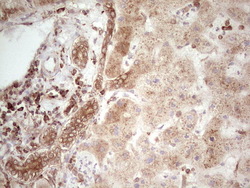

- Main image

- Experimental details

- Immunohistochemical staining of paraffin-embedded Carcinoma of Human lung tissue using anti-WIBG mouse monoclonal antibody. (Heat-induced epitope retrieval by 1 mM EDTA in 10mM Tris, pH8.5, 120C for 3min, TA806496)

- Validation comment

- IHC